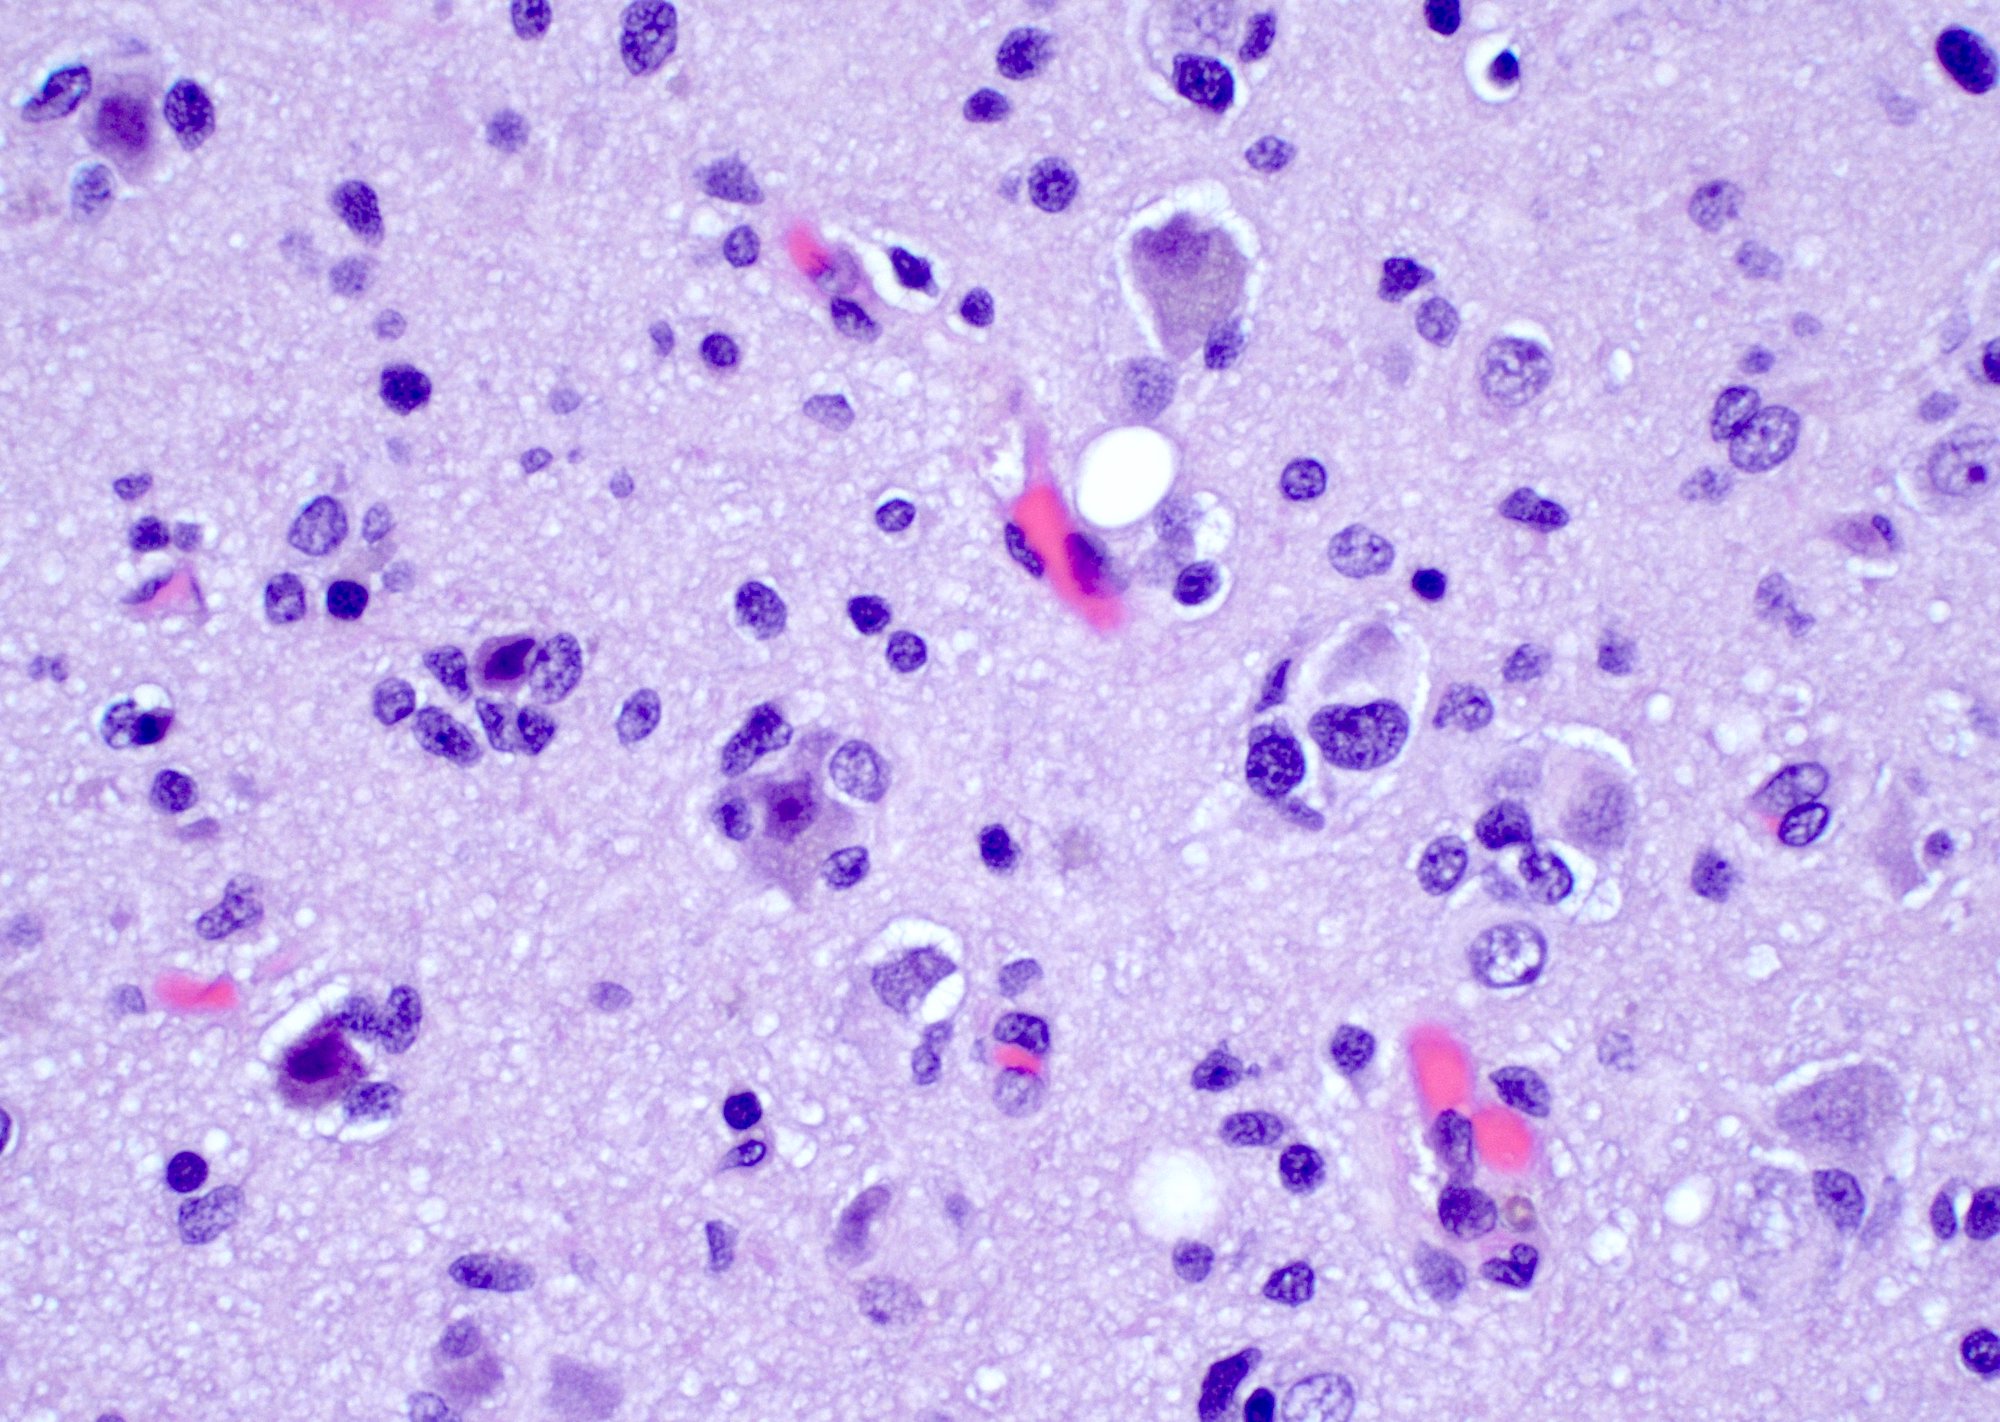

Microscopic (histologic) description

- Infiltrating, hypercellular astrocytic neoplasm often with hyperchromatic, elongated nuclei and irregular nuclear membranes

- Typically mitotically active, though not required if molecular criteria are met

- Microvascular proliferation or necrosis is required for a histologic diagnosis of GBM

- Microvascular proliferation: multilayered, small caliber vessels with glomeruloid appearance (J Neuropathol Exp Neurol 1992;51:488)

- Necrosis: can be geographic or pseudopalisading with neoplastic cells surrounding central necrosis

- Greater association of thrombosis and necrosis in IDH wild type GBM than in IDH mutant grade 4 astrocytomas (Acta Neuropathol 2016;132:917)

- Variable cell morphology: undifferentiated / primitive neuronal cells, astrocytic, gemistocytic, oligodendroglial-like, small cell, lipidized, granular, epithelioid, giant cells, mesenchymal metaplasia and epithelial metaplasia

Microscopic (histologic) images

Contributed by Bharat Ramlal, M.D. and Meaghan Morris, M.D., Ph.D.